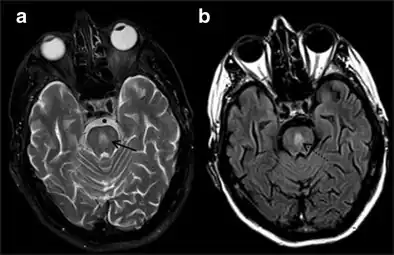

MRI image showing hyperintensity in the pons with sparing of the peripheral fibers, in a person with alcoholism and an initial serum Na of 101 who was treated with hypertonic saline, and developed quadriplegia, trouble talking, and altered mental status.

It can be diagnosed clinically in the appropriate context, but may be difficult to confirm radiologically using conventional imaging techniques. Changes are more prominent on MRI than on CT, but often take days or weeks after acute symptom onset to develop. Imaging by MRI typically demonstrates areas of hyperintensity on T2-weighted images.[27]